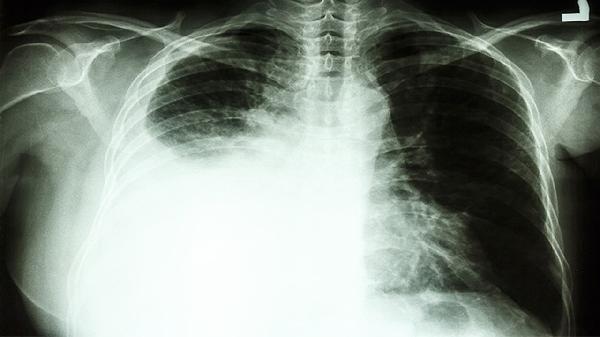

肺癌患者可通過(guò)腹式呼吸訓(xùn)練、縮唇呼吸法、有氧運(yùn)動(dòng)、上肢力量訓(xùn)練、中醫(yī)導(dǎo)引術(shù)等方式鍛煉肺功能。肺癌可能導(dǎo)致肺組織損傷或呼吸肌無(wú)力,需根據(jù)個(gè)體耐受度調(diào)整鍛煉強(qiáng)度。